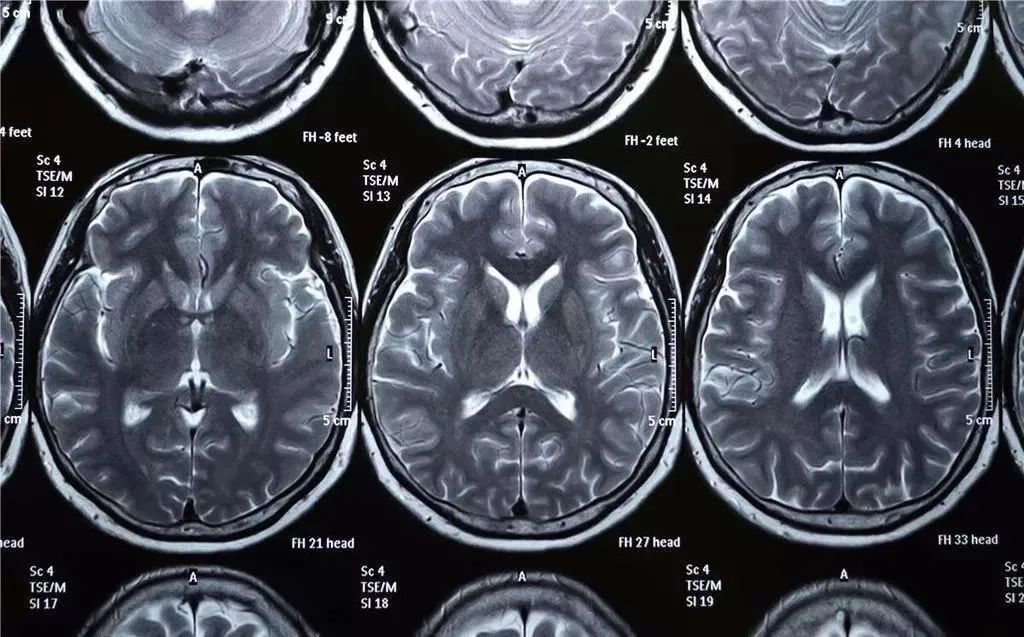

如今,X射线的应用极为广泛。在医学领域,配合现代数字技术,X射线诊断已经可以提供人体内部三维图像;在工业领域,X射线的重大应用是材料无损探伤,可以检测出金属材料和焊接部位的内部缺陷。此外,X射线还应用在微观世界的观察和对太空的研究。